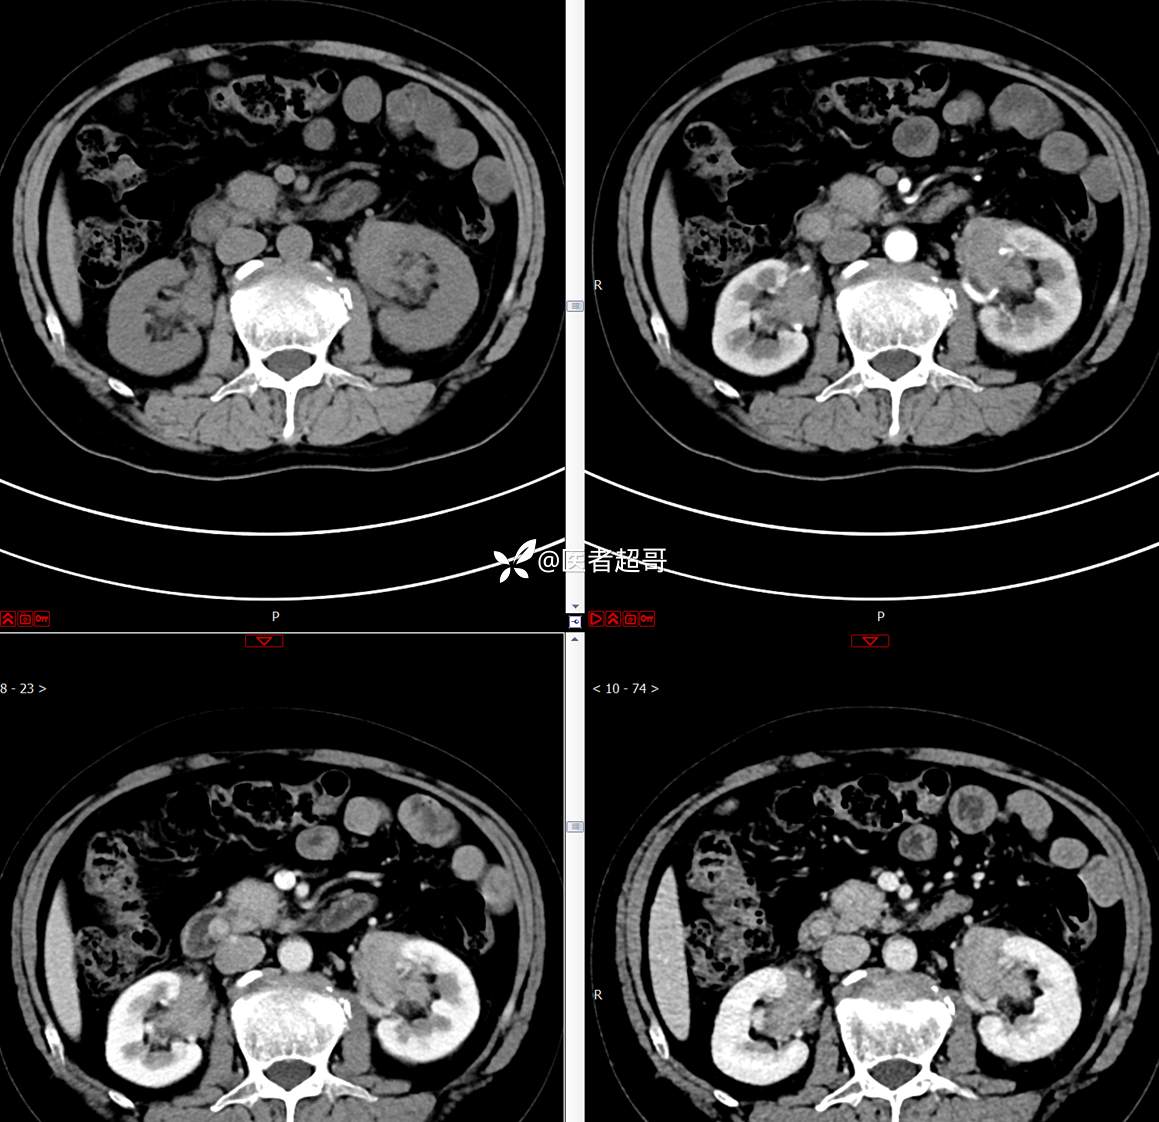

【影诊笔记772】腹痛就诊,发现肾脏病变,CT、MRI齐全,请高诊!

男,63岁 0200825 01

主 诉:间断腹痛15天

现病史:患者15天前无明显原因及诱因出现腹部疼痛不适,呈间断性钝痛,右下腹为著,无尿频、尿急、尿不尽,无发热、寒战,无腹胀。于市中心卫生院住院治疗,超声示:胰头低回声包块,胆系扩张,左肾囊肿,胆囊壁毛糙,胆囊内胆汁淤积。患者为求进一步诊治,遂以“肾盂肿瘤”收入院,患者自发病以来,神志清,精神可,饮食睡眠可,大便无明显异常,近期体重无明显增减。

既往史:既往体健